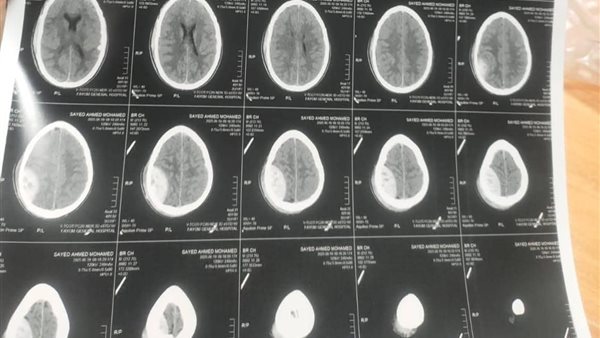

يذكر أن المريض سيد. ا، 39 سنة، كان يعاني من اضطراب بدرجة الوعي بمقياس 15/10، نتيجة حادث سير، وبإجراء الفحوصات تبين وجود نزيف خارج غشاء الأم الجافية بالجانب الأيمن للمخ وكدمة نازفة بالجانب الأيسر للمخ، وتم حجز المريض ودخوله لإجراء جراحة طارئة لتفريغ نزيف خارج غشاء الأم الجافية، وتم تحسن درجة وعي المريض بعد الجراحة مباشرة.